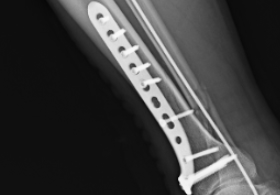

• 5月20日,60歲的王先生(化名)在工地作業(yè)時不慎從1.5米高處墜落,左側(cè)胸部劇烈疼痛,呼吸受限,被緊急送至我院急診科。經(jīng)檢查,患者診斷為左側(cè)多發(fā)肋骨骨折(第4-7肋)、創(chuàng)傷性血氣胸、肺挫傷,且第5肋骨骨折斷端刺入胸腔,情況危急。01多學(xué)科協(xié)作,精準評估創(chuàng)傷中心迅速啟動綠色通道,結(jié)合胸部CT,發(fā)現(xiàn)患者除肋骨骨折外,還合并胸壁皮下氣腫。急診胸部CT:左側(cè)多發(fā)肋骨骨折外科團隊立即會診,認為患者骨折端不穩(wěn)定,骨片可能進一步損傷肺組織,需緊急手術(shù)固定肋骨、避免胸腔出血增多,引起休克。